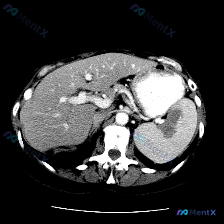

这是一份横断面腹部增强CT(软组织窗)的描述:

- 脾脏:实质内可见片状低密度区,边界相对模糊,位置在脾门附近及脾实质中部;

- 肝脏、胃、血管等:其余腹部实质脏器、腹腔脂肪间隙、脊柱肌肉等未见明显异常;胃腔内有高密度对比剂填充。